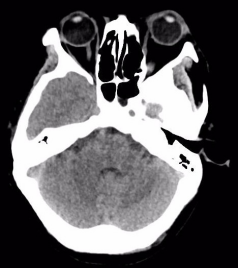

附女士,今年50岁,因车祸头部受伤,意识障碍4小时急诊入院。入院时,患者呈昏迷状,左侧瞳孔散大,头部、腕部、腹部等受伤10余处。急诊CT提示硬膜外血肿,中线移位明显,脑实质明显受压内移,左侧侧脑室受压变窄,病情凶险,手术指征明确。

(术后血肿清除彻底)

术后第一天,患者意识恢复清醒,复查头部CT提示颅内血肿清除彻底。全腹CT、双腕关节CT显示:肠管管壁明显水肿增厚,邻近肠系膜肿胀,肠间隙模糊,盆腔少量积液,腹腔内未见游离积气,提示肠管或肠系膜损伤;右侧月骨脱位,左侧桡骨远端骨折。